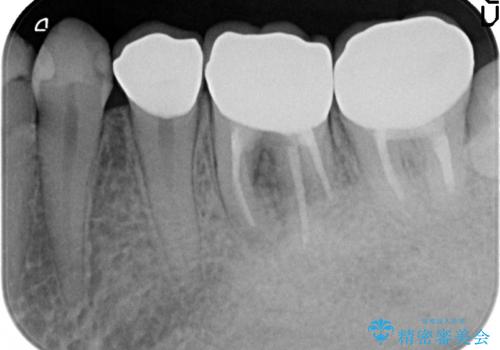

診査の結果、右下6番目の根尖病変を認めたため再根管治療を行いました。

また右下7も根管充填が不十分なため再根管治療を行いました。

症状の消失を確認後、オールセラミッククラウンによる補綴を行いました。